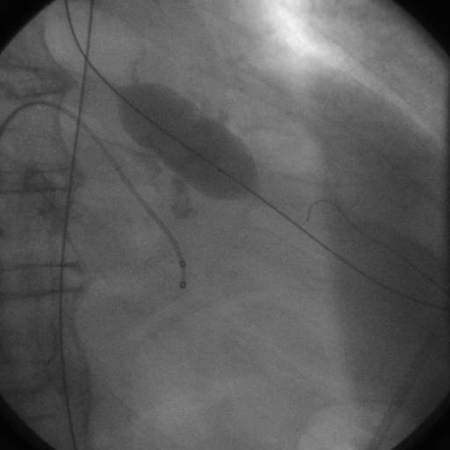

The procedure carries significant risks of acute complications. This is a percutaneous procedure done in the cardiac catheterisation lab in which a balloon is forcefully inflated across the aortic valve to relieve stenosis. Unfortunately, re-stenosis rates are high at 6 months and there is no demonstrated improvement in mortality following valvuloplasty. However, patients do generally experience improvement in haemodynamics and symptoms, which may provide an opportunity for more definitive care.[78]Letac B, Cribier A, Eltchaninoff H, et al. Evaluation of restenosis after balloon dilatation in adult aortic stenosis by repeat catheterization. Am Heart J. 1991 Jul;122(1 Pt 1):55-60.

[Figure caption and citation for the preceding image starts]: Balloon valvuloplasty fluoroscopy film that demonstrates valvuloplasty balloon inflated across a calcified aortic valveFrom the collection of David Liff, MD, Emory University Hospital; used with permission [Citation ends].